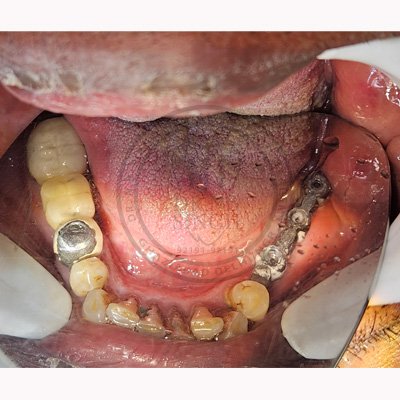

Case – 11 Baleram